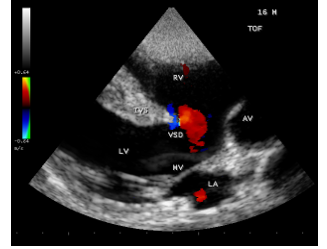

A 16-year-old cyanotic male was admitted with altered sensorium in the intensive care unit. He was diagnosed as Tetralogy of Fallot and advised corrective surgery earlier. He was afebrile and his pulse rate was 64 bpm and blood pressure 100/60 mmHg. He had headache, vomiting episodes and stiff neck for the past 3 days. Blood chemistry revealed normal. ECG and X-ray chest as in Figure 1 (boot-shaped heart) were consistent with Tetralogy of Fallot. Physical examination revealed uniform central cyanosis with clubbing, 2/6 systolic murmur in the left second intercostal space and a single second sound. Echocardiography revealed a non-restrictive, large, malaligned VSD (ventricular septal defect), biventricular aorta as shown in Figure 2. A large vegetation was attached to the crest of interventricular septum (IVS) as in Figures 3 and 4.

Figure 2: showing the large, malaligned VSD (ventricular septal defect) of Tetralogy of Fallot in a 16-year-old boy.

The four components of TOF are ventricular septal defect (VSD), aortic override, right ventricular outflow tract obstruction and right ventricular hypertrophy. In unrepaired TOF, pathophysiology depends on the degree of RVOT obstruction. When obstruction of right ventricular outflow is mild to moderate and a fairly balanced shunt operates across VSD and the patient may not be cyanotic , called as “acyanotic” or “pink” tetralogy of Fallot. The patient may remain relatively asymptomatic until the balance between pulmonary and systemic circulation is disturbed. Echocardiography plays a key role in the diagnosis of infective endocarditis (IE) in TOF. Vegetation may occur on pulmonary and tricuspid valves [42] and a large vegetation occluding the VSD had been reported [43]. In this patient, a large vegetation attached to the crest of interventricular septum was shown in Figures 3 and 4.